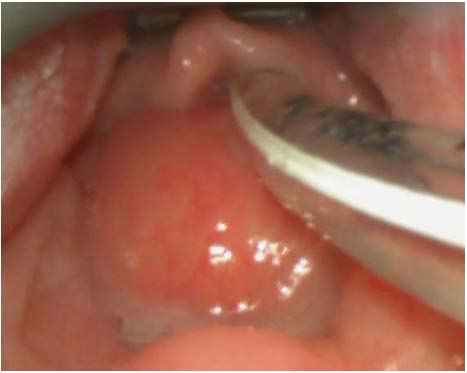

Figure 2: Intraoperative videolaryngoscopy showing bulging of the posterior pharyngeal wall overhanging larynx and obturating piriform sinuses.

figure 2